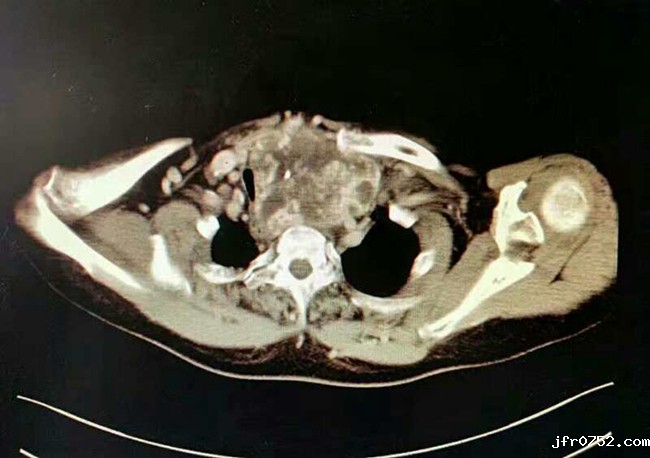

患者,女性,因“阴道不规律出血”入住我院妇瘤病院,诊断为子宫内膜癌,同时发现患有巨大甲状腺肿瘤并深入胸骨后方,气管严重受压变窄,最窄处仅5毫米。若直接行妇科手术,全麻插管困难,且可能出现术后窒息等严重并发症危及生命。不行手术则其妇科疾病难以有效治疗,患者十分着急。我院妇瘤病院赵西侠主任与头颈肿瘤外科梁秦龙主任医师共同会诊后分析,该患者甲状腺巨大肿瘤,深入胸骨后方,气管严重受压变形,且肿瘤与纵膈大血管分解不清楚,手术风险很大。但是如果不先行甲状腺手术,不跨越这个难关,子宫内膜癌手术时无法进行的。所以与家属沟通后先行甲状腺手术。为确保手术万无一失,头颈肿瘤外科赵华、梁秦龙主任团队做了充分的术前准备,并制定详细手术方案。11月16日,在麻醉科陈军主任团队大力协助下,由梁秦龙主任医师主刀,历时1个多小时,成功为患者切除胸骨后巨大甲状腺肿瘤(大小:12cm*10cm*8cm),手术顺利,术后患者恢复良好,第二天即可下床活动,自感呼吸明显通畅,现已转回妇瘤病院进行后续治疗。

胸骨后甲状腺肿瘤因较为隐蔽,不易早期发现,故常病史长,肿瘤巨大,其常伴有气管狭窄麻醉插管困难,另外其紧邻纵膈众多大血管,术中一旦大出血,后果不堪设想,因此此类手术风险极大。该手术的成功实施,再次显示了我院在肿瘤治疗方面雄厚的综合实力,也是我院成功开展多学科协作的又一例典型范例,更为患者后续的治疗铺平了道路。(头颈肿瘤外科 冯海波)